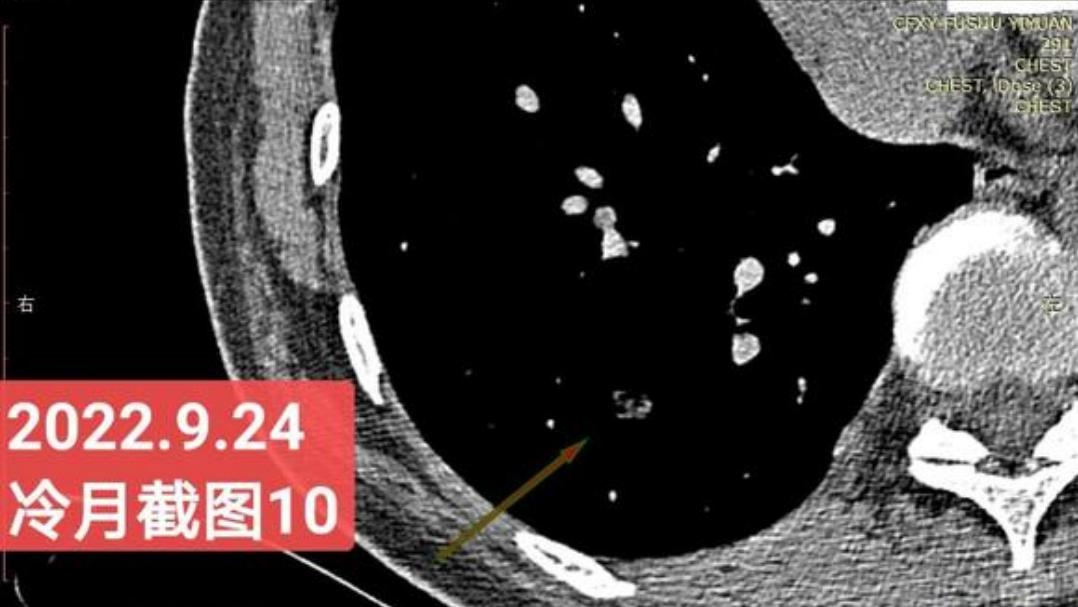

我是21年7月做肺部CT,报告给报出0.5厘米肺结节。(但大夫说,20年就已经有那个肺结节了,因为小,报告没给报)。自发现肺结节后,吃了四个月中药,结节没有缩小,反而增大了。今年8月1日开始到现在,又吃了近两个月的蒙药了。 结节还是没有缩小,反而在增大。21年7月到现在,复查过3次肺部CT了。结节一直在增大。最近一次复查时间是2022年9月24日。

上次找戴主任贴吧咨询过,主任说我右肺下叶那个结节高危,距离上次CT,到现在三个月复查肺部CT。所以9月24日又复查做了肺部CT。

右下肺结节高危,肺窗已经到亚实性阶段CTR>0.5,纵膈窗可见实性,目前已经不属于异质混磨,而且PSN亚实性结节。